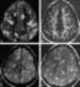

Cysticercus

Cysticercus (pl. cysticerci) is a scientific name given to the young tapeworms (larvae) belonging to the genus Taenia. [Source: Wikipedia ]